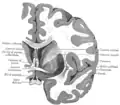

Корональний розтин мозку через передню спайку.

Горизонтальний розтин правої півкулі головного мозку.